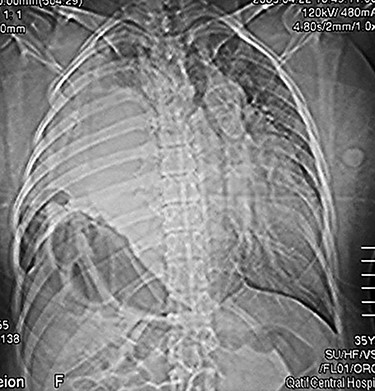

Abdominal CT scan with contrast showing the entire liver and some bowel loops occupying the right hemi-thorax.

showed the entire liver and some bowel loops in the right hemi-thorax (Fig. 2). The impression was right diaphragmatic herniation, although ruptured right hemidiaphragm was entertained despite the negative history of chest trauma.